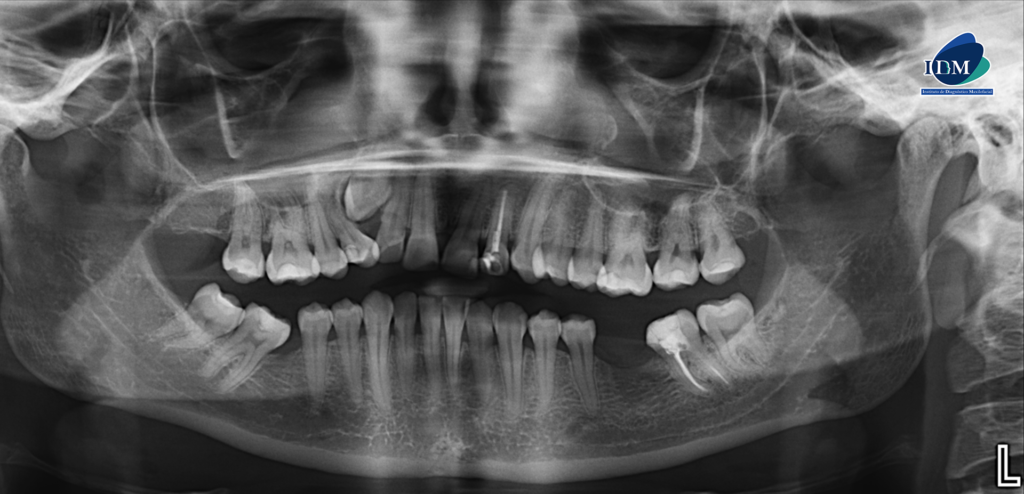

En la radiografía panorámica (Figura 1), se observa pieza 33 con pérdida del lumen del conducto radicular a nivel del tercio medio y apical.

Radiografia Panorámica